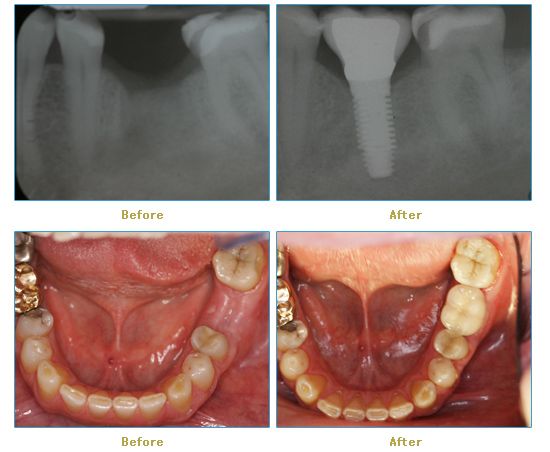

Dr. Cabianca has restored hundreds of smiles through the latest techniques in restorative and cosmetic dentistry. The following before and after photos document a few such cases in which Dr. Cabianca has replaced and reshaped teeth to produce wonderful smiles. Click on any of the images below to view larger versions of the photos.